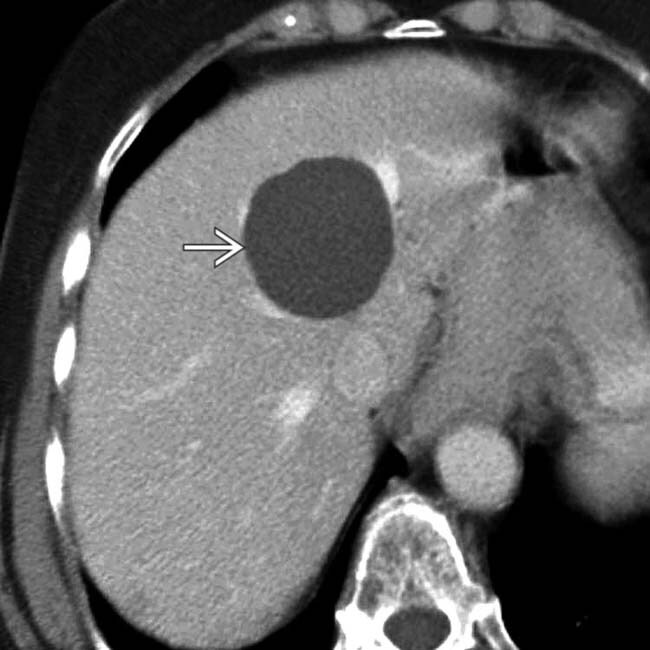

HNF (hiperplasia nodular focal)

2 mais comum

crescimento segmentar do fígado hiperproliferação hepatocitária benigna (secundário a presença de artéria anômala ?)

lesão hipervascularizada hipercaptante e presença de cicatriz central (achado presente em 40%)

Não tem canaliculos biliares - > hiperrealce na fase hepatobiliar (na RM com primovist)

cd: conservadora, exceto se sintomáticos ou duvida diagnostica